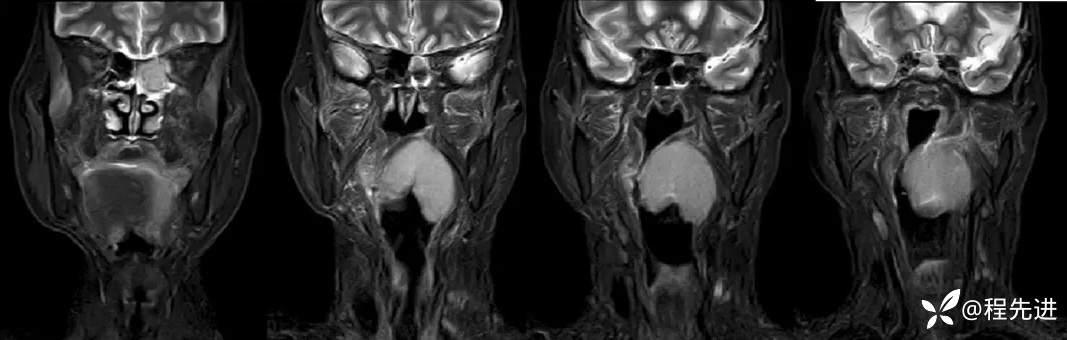

MRI平扫+增强:

T2:

T2压脂: